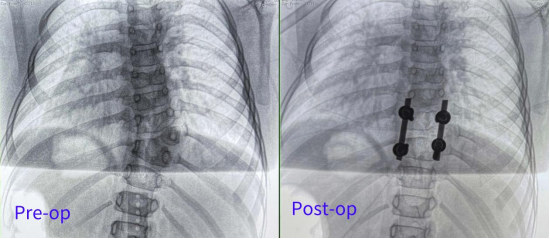

Patient: Female, 5 years old

Clinical Symptoms: Asymmetrical back, uneven shoulders, scoliosis

Surgical Indication: Congenital hemivertebra deformity accompanied by scoliosis, which affects normal growth and development. Surgical correction was necessary. Early surgical intervention can effectively prevent deformity progression and improve prognosis.

Surgical Approach: Posterior hemivertebrectomy combined with short-segment fixation and fusion

Surgical Goals: Eliminate the deforming element, correct spinal deformity, restore spinal balance, and preserve the patient's growth potential.

Fluoro-verified precise screw implantation